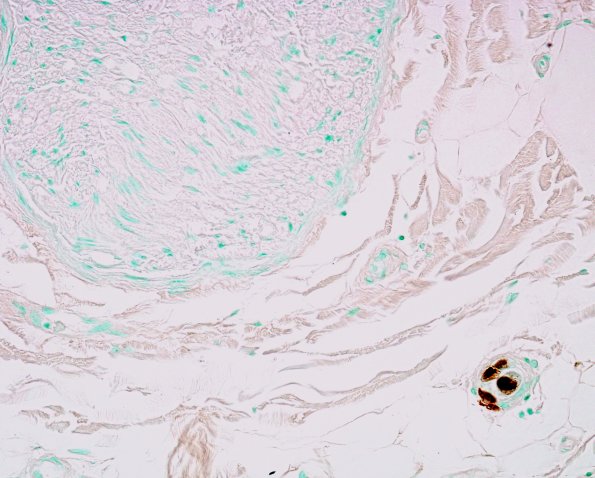

These lightly stained images show CMV immunoreactive elements, sparing the endoneurium. (CMV IHC)